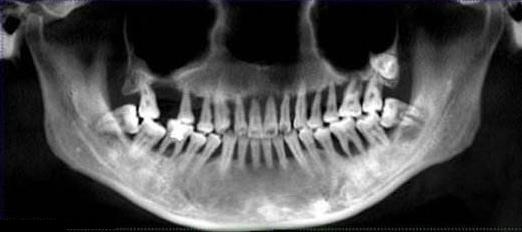

嚴(yan) 重牙周病造成全口牙齒無法保留的情況

天然牙和兩(liang) 顆種植假牙(紅圈內(nei) )